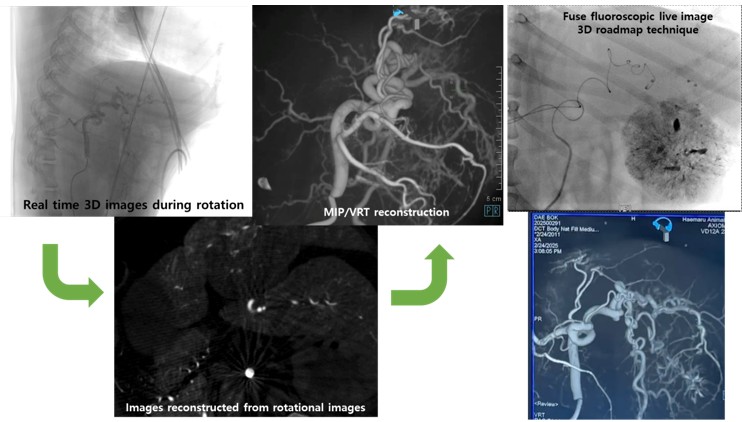

이번 발표는 해마루동물병원이 지난 2024년 12월 전 세계 동물병원 최초로 도입한 독일 지멘스사의 3차원 혈관조영장비인 ‘아티스큐 씰링(Siemens Artis Q Ceiling)’을 이용해 진행한 간암색전술 18건에 대해 회고 분석한 결과를 바탕으로 이루어졌다.

인의에서는 3차원 혈관조영장비를 이용한 간암색전술이 이미 표준 치료 방법으로 이용되고 있다. 기존 하이엔드 C-arm을 이용한 시술 대비 우수한 치료 효과 및 낮은 부작용을 보인다고 보고되고 있다.

전성훈 센터장은 발표에서 “3차원 혈관조영술을 이용할 경우 간암으로 공급되는 영양동맥을 보다 정확하게 파악할 수 있고, 간 내에 위치하는 영양동맥뿐만 아니라 간 외에서 공급되는 영양동맥(collateral/extraphepatic feeding artery)까지 직접 확인할 수 있어 더 세밀하고 정확한 치료가 가능하다”고 설명했다.